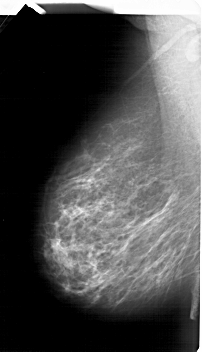

A_1485_1.LEFT_CC

LEFT_CC LINES 6691 PIXELS_PER_LINE 3766 BITS_PER_PIXEL 12 RESOLUTION 43.5 NON_OVERLAY